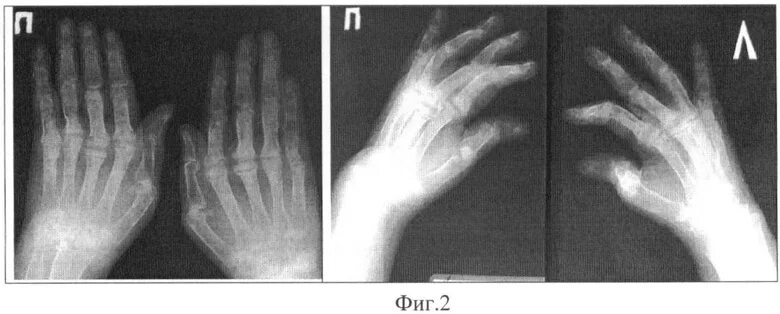

Ульнарная девиация кисти ревматоидный артрит. ульнарная девиация кисти рентген. типы деформации кисти при ревматоидном артрите.

Ревматоидный артрит деформация кисти. ревматоидный полиартрит рентген. ревматоидный артрит запястного сустава. полиартрит рентген кистей.

Рентгенологические стадии ревматоидного артрита. паукообразная кисть ревматоидный артрит. ревматоидный артрит кисти рентген. ревматоидный артрит пястно фаланговый сустав.

Ревматоидный артрит кисти рентген. ревматоидный артрит деформация кисти. полиартрит рентген кистей. ульнарная девиация кисти рентген.